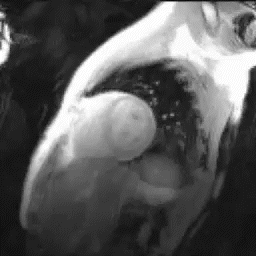

心臓MRI検査

MRIにより心臓の筋肉の状態や動きを見る検査。シネMRI撮影では心臓の動きを動画で確認ができます。

出典: the University of Minnesota | Atlas of Human CARDIAC Anatomy

http://www.vhlab.umn.edu/atlas/index.shtml